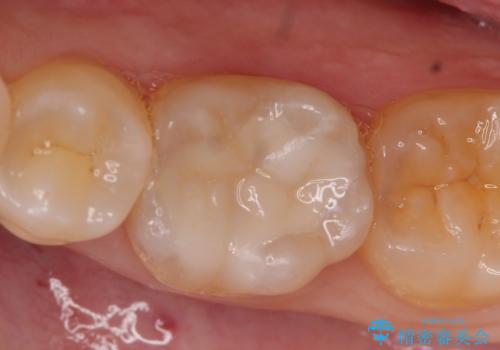

セラミックインレー しみる奥歯の治療